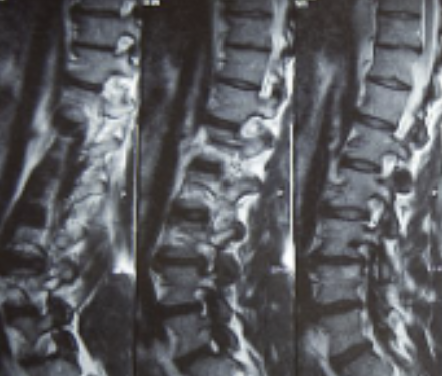

허리디스크는 디스크가 터져서 신경을 누를 경우 생기는 것으로 보통 4,5번에서 많이 발생하고 디스크가 터진 양이 적다면 터진 순간부터 수분이 날아가면서 양이 많이 없어지는데 그렇지 않고 양이 많을 경우 극심한 통증이 생깁니다.

허리디스크를 정확하게 진단하기 위해서는 엑스레이로는 힘들며, MRI를 통해 검사해야 정확하게 볼 수 있습니다.

MRI가 몸에 좋지 않지만 허리 통증으로 엑스레이만 진행 할 경우 오진이 많아 지속적인 통증이 계속 된다면 허리디스크를 의심하고 MRI 검사를 한번 받아보시길 권유드립니다.